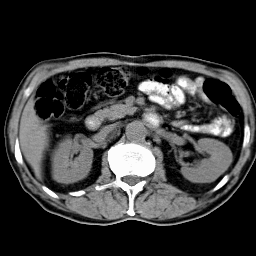

Это конфигурация для работы с изображениями. На рисунке видны два главных окна системы: окно Управление (справа) и окно Изображения, с изображением среза, полученного на рентгеновском томографе.